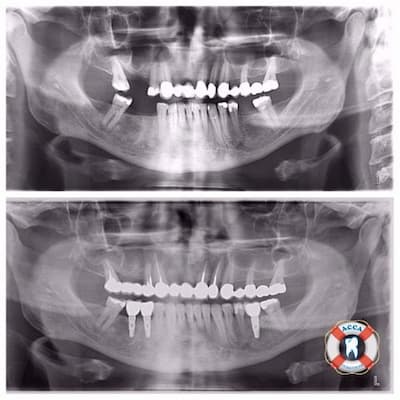

Фотографии ортопантомограмм и работ Родена